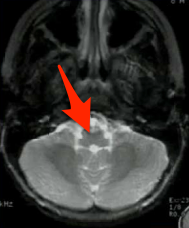

What structure is indicated below?

Medulla. Note that it looks like a butterfly.